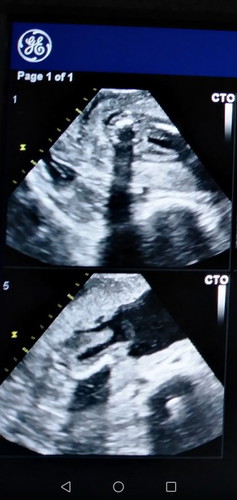

สอบถามค่ะ ท้องได้ 19 วีคแล้วค่ะ ลองซาวด์ดูเพศ ไม่แน่ใจได้ชายหร่อ หญิงค่ะ คุณหมอดูคร่าวๆ น่าจะ ได้ ผู้หญิงค่ะ นี่ท้องที่3ค่ะ สองคนแรก ผู้ชายค่ะ ??

ไม่ชัดเลยจ้า รอหมอคอนเฟิร์มดีกว่าค่ะ